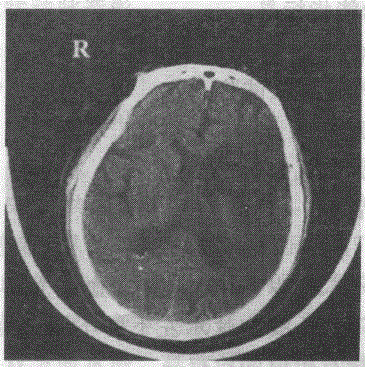

问题 某高血压患者出现偏瘫,CT如图,该患者可能出现下列哪种表现

选项 A.左侧肢体无力 B.右侧肢体无力 C.左侧肢体感觉减退 D.胸4以下感觉减退 E.双侧下肢振动觉消失

答案 B